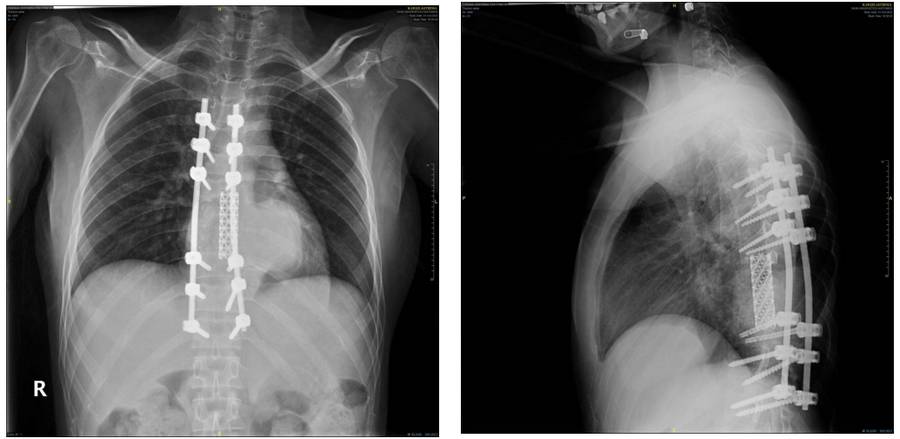

Ameliyat öncesi: Röntgende daha önceki ameliyatlarda uygulanan enstrümentasyon ve cage ile birlikte nüks tümörün yumuşak doku gölgesi görülmekte

Ameliyat sonrası: Röntgende korpektomi sonrası fibula, cage ve enstrümentasyon uygulaması görülmekte